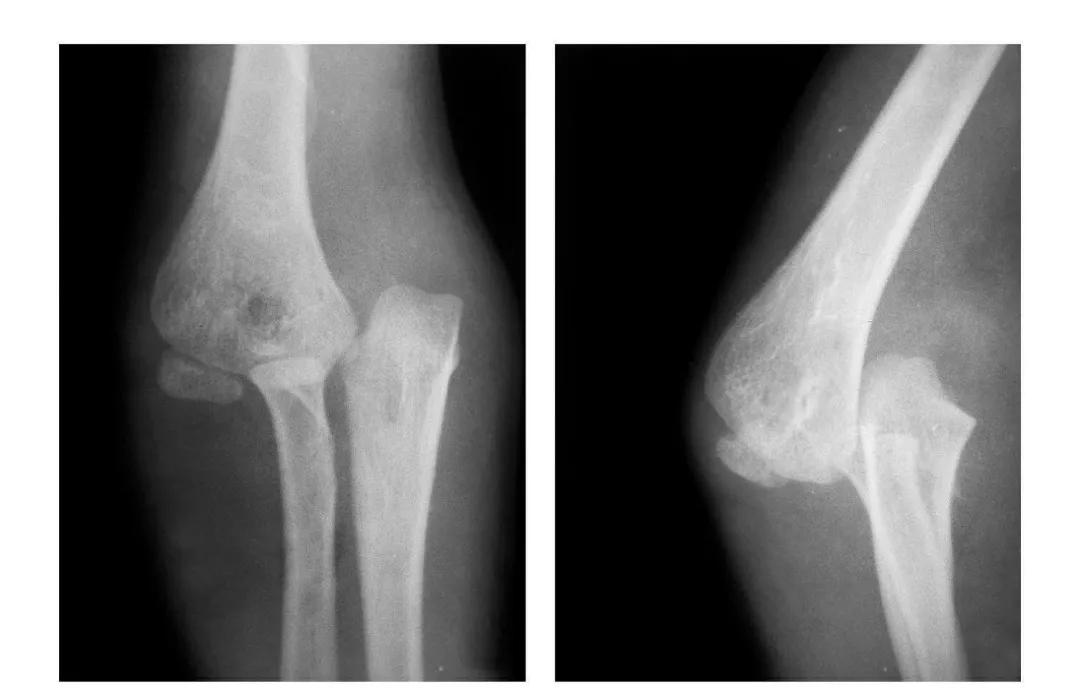

肱骨小头冠状面骨折

(一)完全骨折

本病亦称哈-斯(Hahn-Steinthal)型骨折

例1:肱骨小头基底部呈冠状面骨折,骨折块呈半球状向肘前上方移位。

例2:肱骨小头基底部冠状面骨折,骨折块呈半球状向肘前移位并肱骨内上髁无移位骨折。

例3:肱骨小头及滑车桡侧壁前半部呈整体性冠状面骨折,骨折块向前上移位并外髁骨折。